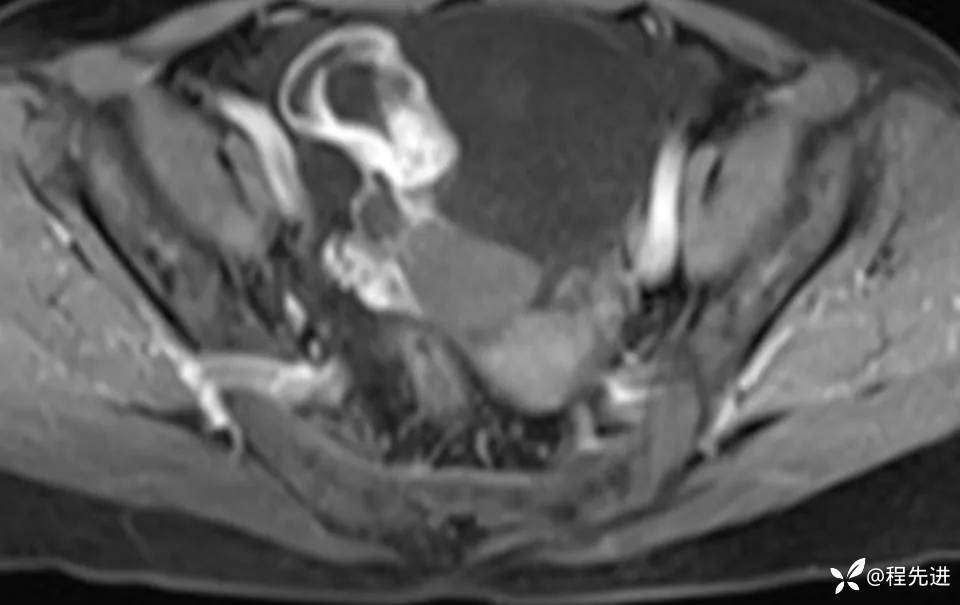

MRI平扫+增强: